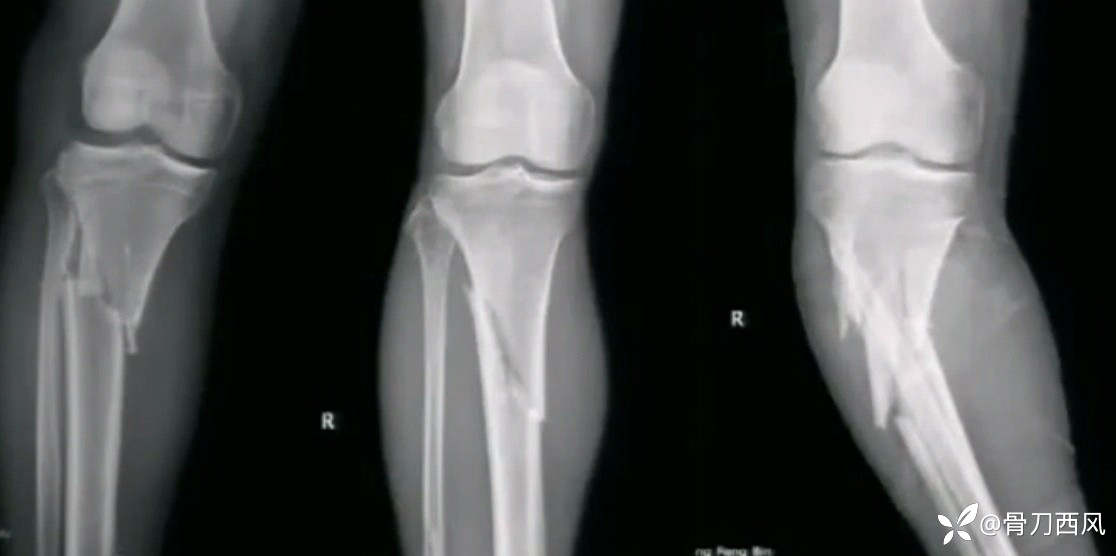

胫骨骨折,髌上或髌下,如何选择?

病例信息